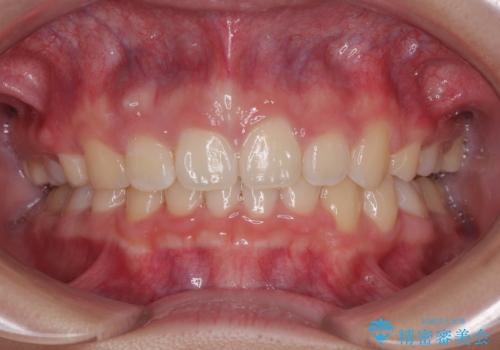

上下正中位置を改善するため、左下はイレギュラーに第二小臼歯を抜歯しました。そのため治療期間の長期化が予想されましたが、2年半ほどで期待通りの歯列に仕上げることができました。

また、上顎歯列が下顎に対して前方位に位置していたため、補助装置を用いて上顎歯列を後方に移動させ、より積極的に口元を下げるようにしました。